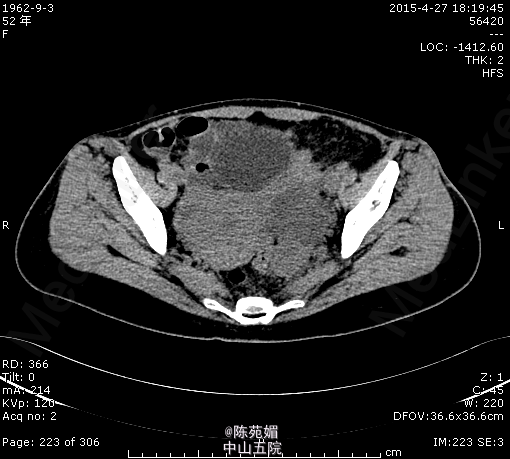

入院诊断:1.腹痛、发热查因:急性肠胃炎?2.地中海贫血3.脾切除术后。入院后我院腹部CT示:左附件区混杂密度肿块,建议进一步检查。血常规示:WBC 19.05×10^9/L,HB 88g/L,余肝肾功能未见明显异常。请妇科会诊,考虑左附件脓肿形成可能性大,遂转妇科进一步治疗。感染控制后,行腹腔镜下左附件切除术。术中见左侧附件肿大,被乙状结肠和直肠包裹,分离粘连后见左侧输卵管卵巢膨大、水肿,破裂后流出黄白色脓液,切除左侧卵巢、输卵管。术后病理示:符合脓肿组织学图像。